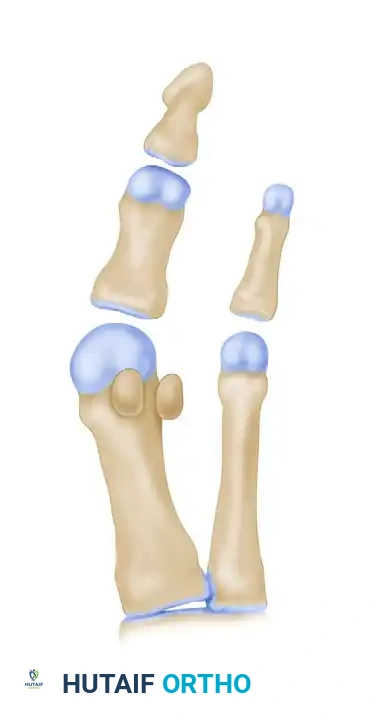

يحدث انحراف إصبع القدم الأكبر عندما تبدأ عظمة المشطية الأولى في الانحراف نحو الخارج بعيدا عن باقي عظام القدم، بينما ينحرف إصبع القدم الأكبر نفسه نحو الداخل باتجاه الأصابع الأخرى. هذا الخلل في المحاذاة يؤدي إلى بروز نتوء عظمي عند قاعدة الإصبع الكبير، وهو ما يسبب الألم والالتهاب عند احتكاكه بالأحذية.

تستهدف عملية سكارف هذا الخلل الميكانيكي في جوهره. فبدلا من مجرد إزالة النتوء العظمي البارز وهو إجراء لا يحل المشكلة الأساسية وغالبا ما يؤدي إلى عودة التشوه، تقوم هذه الجراحة بإعادة هيكلة العظمة المشطية الأولى بالكامل، وإعادتها إلى مسارها الطبيعي والصحيح، مما يضمن نتائج طويلة الأمد ووظيفة حركية سليمة للقدم.